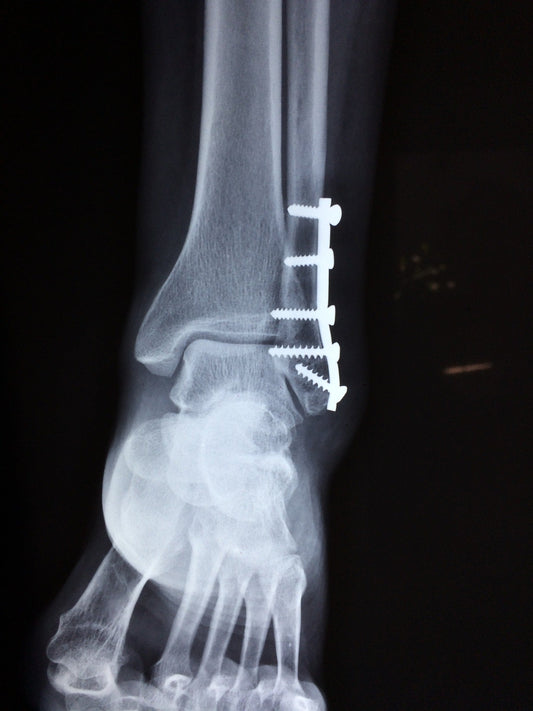

What Is The Fastest Way To Recover From Ankle S...

People undergo ankle surgery for a variety of reasons and the goal can vary depending on what issue(s) a patient is suffering from. Just as there are different reasons for needing...